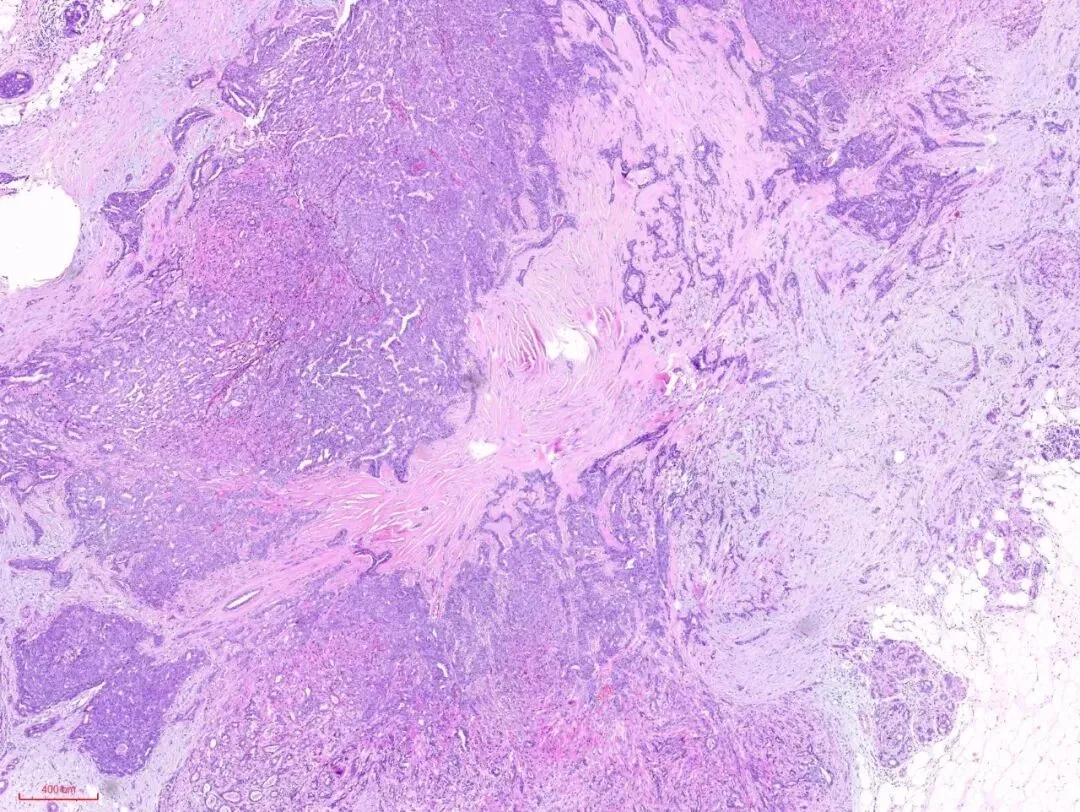

这是低倍镜下的一张图片,纤维结缔组织大量的增生→会挤压包裹其中的腺体→被挤压的腺体扭曲、变形、拉长。如下图:

在没有粉染的硬化的间质旁边,似乎可以看到小叶的特化性间质。

这是另一例,低倍镜下观察, 硬化型腺病的部分似乎保持小叶中心性的分布模式,病变周围是正常的小叶,如图:

在视野中心看到粉染的硬化的纤维结缔组织,其内有受挤压变形的腺体,其周边有增生的腺体,如下图: